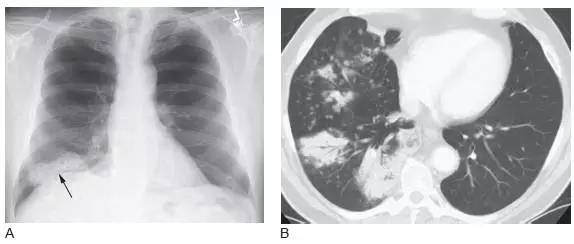

图1 表现为支气管管腔内和肺门肿块的鳞状细胞癌

A.CT 显示右下叶支气管内息肉状的肿块( 箭头),为典型的鳞状细胞癌;

B. 在稍低层面,支气管腔阻塞伴局部浸润,导致肺门肿块(M)